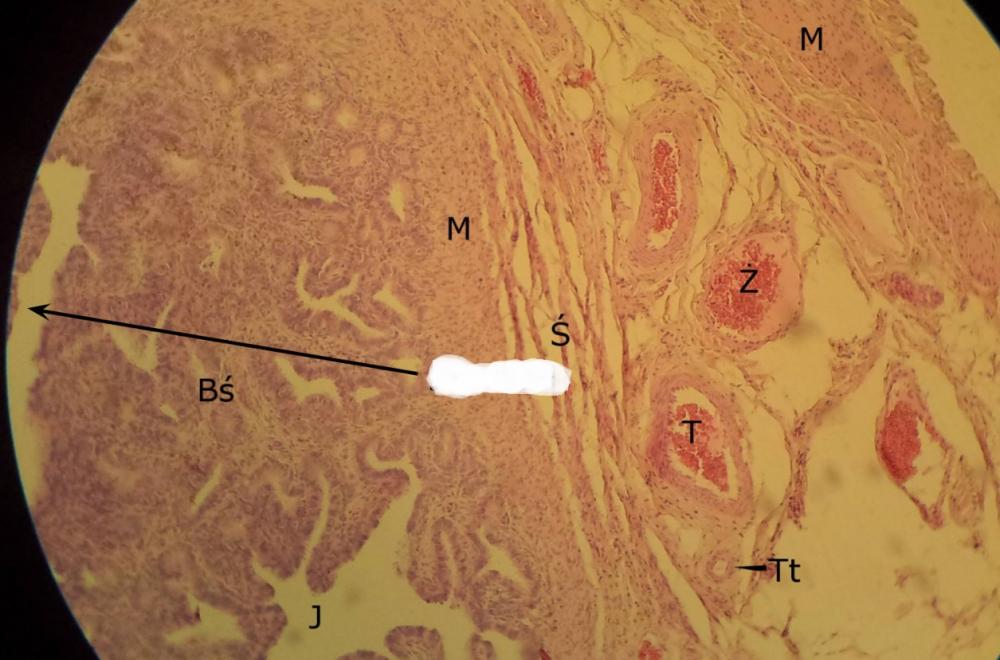

Pytanie 481

pęcherzyk wzrastający bezjamisty (jajnik, kora)

Pytanie 482

tętnice (jajnik, rdzeń)

Pytanie 483

gruczoły śródmiąższowe - ciemne komórki (jajnik, kora)

Pytanie 484

jajowód (jajnik, rdzeń)